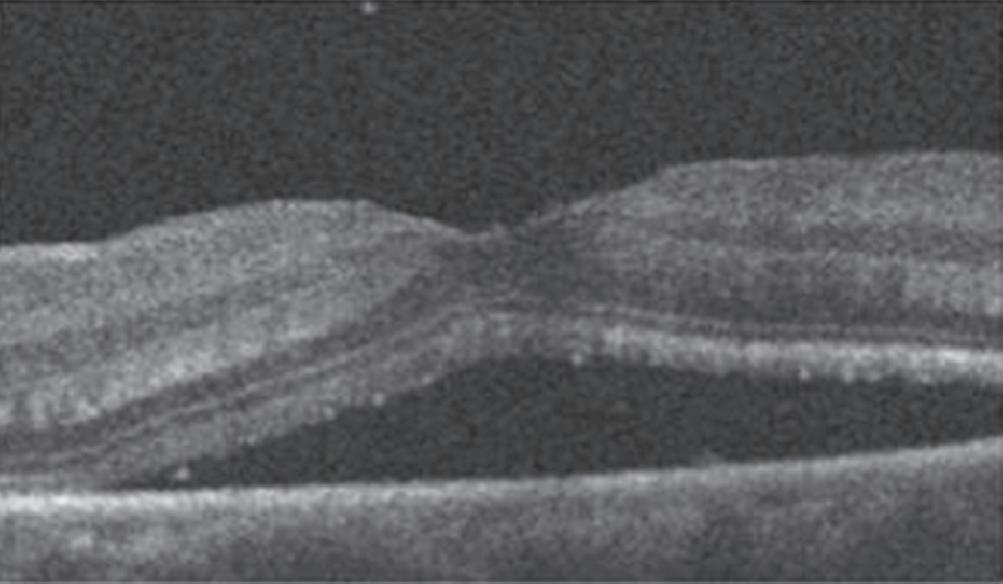

Um exemplo da capacidade da OCT para prever a acuidade visual pós-operatória em olhos com descolamento de retina regmatogênico (RRD) sem mácula está na Figura 1-27.20 Outras áreas da medicina se beneficiam igualmente da técnica da tomografia de coerências ótica . Para citar algumas: dermatologia no diagnóstico de lesões da pele como carcinomas etc. Na cardiologia se usa para obter imagens de alta resolução das artérias coronárias. O método de OCT por endoscopia foi introduzido em 1997 pelo pesquisador James Fujimoto no MIT e outros colaboradores. Finalmente, na indústria de semicondutores na medição não destrutiva das camadas finas dos seus dispositivos. O campo das aplicações do uso da OCT é cada vez mais amplo e se pode afirmar que novos e melhores equipamentos estão por vir.

1-27. Imagens pré-operatórias de tomografia de coerência óptica (oCT). Um círculo com um diâmetro de 2 mm foi posicionado manualmente no centro da superfície foveal da mácula destacada na imagem de oCT. a área macular dentro do círculo foi dividida em três seções: camada interna (superior direita: camada de fibras nervosas e camada de células ganglionares), camada intermediária (inferior direita: camada plexiforme interna e camada nuclear interna) e camada externa (inferior esquerda: camada plexiforme externa e camada nuclear externa). (reproduzida com permissão de https://www.hindawi.com/copyright/.)20